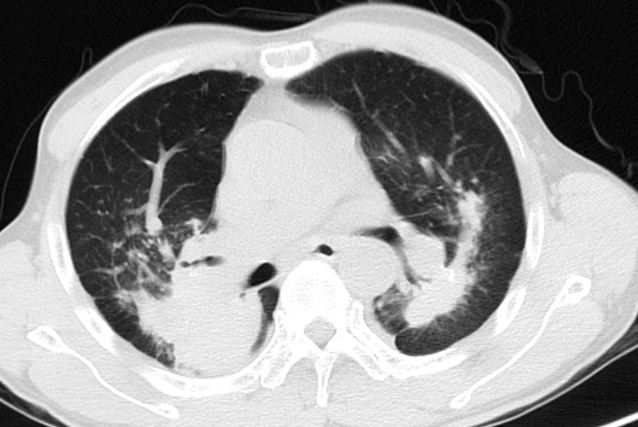

【病例会诊】尘肺,感染,肿瘤(关系) [病例帖]

图片尺寸2311x1871